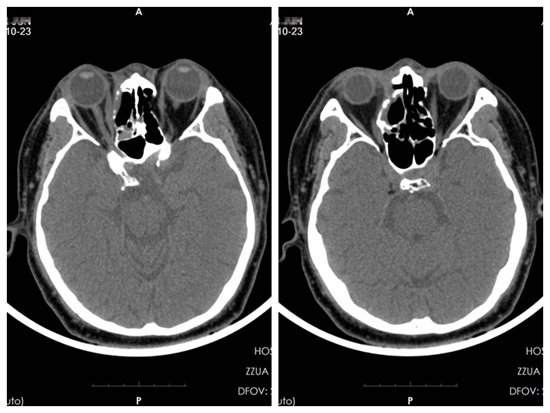

2017年的7月份,张大哥被检查出鼻窦囊肿,原以为只是普通的肿块,怎料,短短一个多月,肿块就将右眼球挤出了眼眶,右眼下方的白眼球变得异常明显,眼睛酸痛肿胀、流泪,由于眼球严重外突,两个眼睛的视距无法统一,导致张大哥不能继续开车。事实上,比起给自己生活上造成的不便,张大哥更怕的是别人用异样的眼光看待自己。辗转多家医院就诊,CT提示:张大哥的右侧鼻腔及筛窦占位,病变突破眼眶外侧壁向外生长,右侧眼眶内直肌受侵,病变最大直径4.5公分,考虑鼻腔鼻窦恶性肿瘤局部晚期。在张大哥看来,这份检查结果无疑是给自己判了死刑,考虑到要保留面部器官的完整性,因此无法手术,只能采用放化疗治疗。

患者放疗前CT图

患者放疗中CT图

如今,张大哥已经接受了27次放疗,2次化疗,右侧鼻腔鼻窦的肿瘤已经完全消失,右眼外观与常人无异,右眼视力无明显下降。“医生说我马上就能出院了,能开车了,也能跟朋友一起吃饭、唠嗑了,这搁以前,我真是想都不敢想吶!”张大哥笑着说道。

患者放疗后CT图